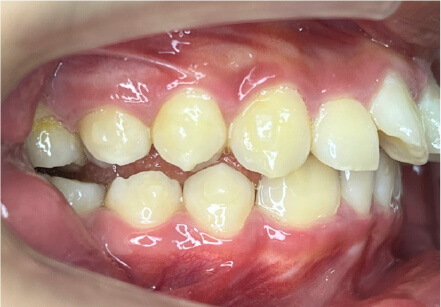

叢生の症例

11歳

女性

相談内容

上の前歯の歯並びが気になる(マイオスマイルからの移行)

カウンセリング・診断結果

インビザライン、拡大入れながらスペースを作成、下Eは出てきたら削りながら進める

治療内容・方法

全額アライナー矯正 クリアコレクト

術後の経過・現在の様子

クリアライナー使用

治療のリスク

痛み・歯根吸収・歯肉退縮・虫歯・後戻り

費用・治療期間

移行料金220,000円、月々16,500円、1年1ヶ月+myo2年3ヶ月